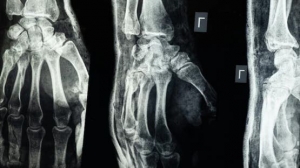

وجال الوزيران في القسمين واطلعا على التجهيزات الجديدة، بما فيها محطة تحلية المياه الخاصة بأجهزة غسيل الكلى، واستمعا إلى المرضى حول جودة الخدمات المقدمة، كما تفقدا جاهزية جهاز الرنين المغناطيسي بعد إصلاحه وإعادة تشغيله عقب سنوات من التوقف.

وأوضح مدير المشفى أمين سليمان أن المشفى شهد إعادة تأهيل شاملة، وأصبح مصدر ثقة للمواطنين بعد التحرير، حيث شملت إعادة التأهيل رفد مركز غسيل الكلى بـ 32 جهازاً حديثاً وتجديد البنى التحتية، إلى جانب إصلاح جهاز الرنين المغناطيسي، ما ساهم في رفع الطاقة الاستيعابية وتحسين جودة الخدمات.

وبيّن رئيس شعبة الكلية في المشفى، قاسم باشا، أن القسم الجديد استلم 21 جهازاً متطوراً من نوع “فريزينيوس 5008 S”، إضافة إلى 8 أجهزة من الطراز القديم، ليصبح المجموع 29 جهازاً تعمل بتقنية “الهيموديافلتريشن” المتقدمة، والتي تتجاوز الوظيفة التقليدية لغسيل الكلى، مشيراً إلى تحسن ملحوظ في حالة المرضى بعد شهر من الاستخدام.